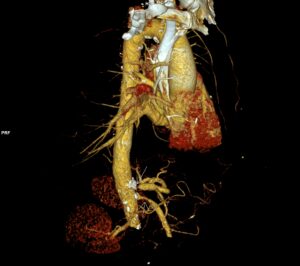

Examenul fluoroscopic al diafragmei (testul mirosului „sniff test”) este util în diagnosticarea paraliziei diafragmatice. La indivizii normali, ambele hemidiafragme coboară de obicei cu inspirație. În cazurile de paralizie diafragmatică unilaterală, partea afectată poate demonstra o mișcare ascendentă paradoxală.

Ecografia este un bun înlocuitor pentru fluoroscopia și poate fi efectuată la pat cu pacientul întins, dacă poate respira în această poziție. Este mai ușor să evaluezi copiii cu ultrasunete cu evitarea riscul de iradiere. Ecografia în timp real este efectuată în plan axial pentru a compara cele două hemidiafragme simultan. Modul M suplimentar coronal sau sagital poate ajuta la cuantificarea gradului de mișcare a fiecărui hemidiafragm individual. Criteriile de diagnostic la copii includ mișcarea paradoxală, excursia mai mică de 4 mm și o diferență >50% între excursia unui hemidiafragm față de celălalt.

Justificarea iradierii este făcută de către medicul radiolog; la pacienții care postoperator în sfera cardiacă prezintă dificultăți la detubare și se suspicionează o hernie diafragmatică, ecografie este de mare ajutor pentru diagnostic – cu avantajele că se efectuează la pat și evităm iradierea nenecesară.